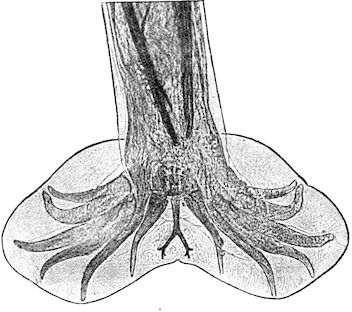

Fig. 1.—Rachitis in a young goat.

Rachitis is a disease of youth, and is common both to the human species and to all domestic animals. It is characterised by irregularities in development and by imperfect consolidation of the bones. The boundary between rachitis and osseous cachexia is difficult to define and in fact at the present moment the two diseases can scarcely be defined with exactitude. Rachitis again is often complicated with softening of the bones, disease of the limbs, arrested development, etc., but it must not be forgotten that although the irregularities in ossification and development of the skeleton are the symptoms most striking to the eye, they do not stand alone, and that from the point of view of development all the tissues, including the muscles, are more or less affected and that most of the physiological functions such as digestion and the secretion of urine are deranged.

Symptoms. The onset is absolutely insidious and the diagnosis of rachitis is never made until nutrition has long been abnormal.

This disturbance of nutrition is revealed by irregularity and abnormality in appetite, by difficulty in rising and moving about, and by the animals lying down for long periods. The subjects are feeble, sluggish and badly developed.

Next supervenes the second phase characterised by deformity of bones. This is of two kinds—deformity in the neighbourhood of joints (deformity or enlargement of the epiphyses) and deformity of the diaphyses. The former results from irregularity in ossification of the articular cartilages. The latter is followed by loss of rigidity in the bones of the limbs which, under the influence of the body weight and of muscular contraction, bend in different directions.

The bones appear of increased thickness principally towards the 6articulations. The latter are deformed, and on palpation are found to be surrounded by uneven and irregular growths.

The front limbs are distorted. In young pigs, lambs, and less frequently in foals, calves and dogs, the jaws become deformed, and mastication is rendered difficult.

The vertebral column may also be affected, and lordosis (bending downwards of the back) or skoliosis (lateral bending of the back) is somewhat frequent.

Cyphosis, or upward bending of the back, seldom occurs, and when seen, sometimes results from disease other than rachitis.

General development is always interfered with and the young creatures are generally dwarfed.

The digestive apparatus is disordered, the appetite is irregular and sometimes depraved, while indigestion, gastritis, and enteritis are not exceptional. Physiological and pathological research has shown that the quantity of phosphoric acid eliminated in twenty-four hours in a rachitic child is double the quantity passed by a healthy infant. The amount of urea in the urine (which is a criterion of nutrition, and usually varies in proportion to the amount of food ingested) is, on the contrary, diminished even when highly nitrogenous food is given, thus suggesting diminution in nutrition.

Lesions. The lesions are represented by abnormal and irregular thickening around the interarticular cartilages. The cartilage is thickened, compressible, very spongy and without regular ossification. Diffused periostitis exists principally towards the extremities of the bone. Beneath the periosteum the surface of the bone appears rough and softened. On section the medullary canals are seen to be enlarged and filled with marrow of a gelatinous character. The Haversian canals are dilated, and the entire tissue appears very vascular. Chemical analysis proves that the mineral constituents of the bone, particularly the phosphates, have diminished by one-half; the organic constituents on the other hand are increased in a similar ratio, but the ossein is abnormal. Ossification has, in a word, been incomplete.